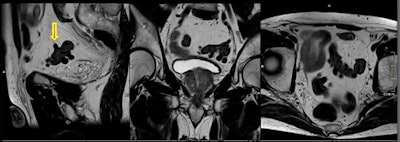

74-year-old man with diverticular disease. Incidental finding on prostate screening: multiple diverticula of the sigmoid colon without evidence of diverticulitis.- Inflammatory bowel disease: This term is used for two conditions (Crohn's disease and ulcerative colitis) that are characterized by chronic inflammation of the gastrointestinal (GI) tract. Prolonged inflammation results in chronic damage to the GI tract.